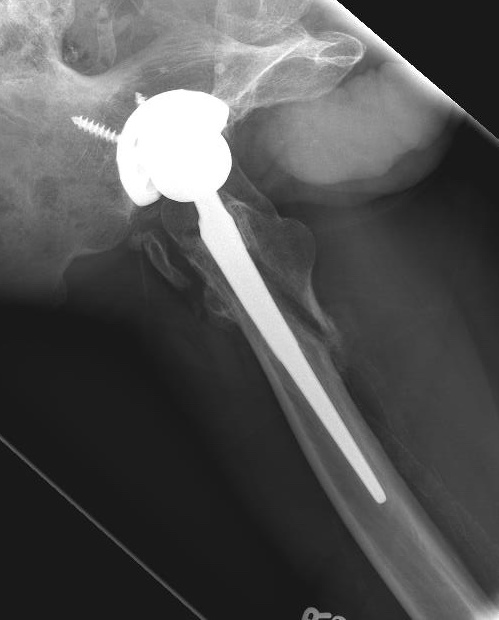

Long stem uncemented revision

Revision uncemented arthroplasty with Zimmer cable plate